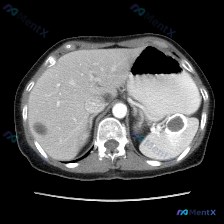

最近看到一份腹部CT平扫的病例资料,最初的关注点被引向了“脾脏病变”,但仔细读完整份影像分析后,发现思路需要完全调整——整理一下这个过程,挺有警示意义的。 --- 先看影像里的客观发现 这份是腹部CT软组织窗横断面的平扫影像: 1. 脾脏:形态正常,实质密度均匀,未见明确占位性病变; 2. 肝脏:轮...